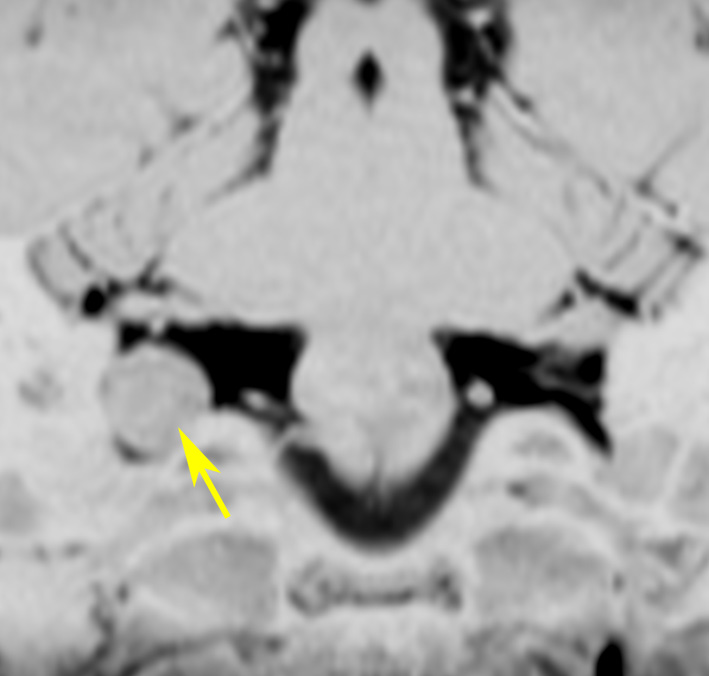

症例:小脳延髄角槽のもの,頸静脈孔へ少し入るもの

30歳くらいの女性に発生した無症状のものです。矢印のように拡大した頸静脈孔へ少し入っています。定位照射でもよかったかもしれませんが,若い女性なので手術しました。